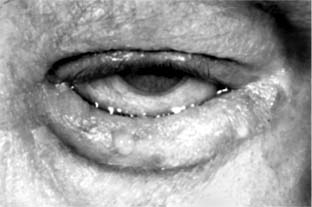

Congenital anomalies of the canalicular system include imperforate puncta, accessory puncta, canalicular fistulas, and, rarely, agenesis of the canalicular system. Most cases of canalicular stenosis are acquired, usually the result of viral infections-notably varicella, herpes simplex, and adenovirus infection. Obstruction-even obliteration-may occur with Stevens-Johnson syndrome, pemphigoid, and other conjunctival shrinkage diseases. Systemic chemotherapy with fluorouracil and topical idoxuridine may also cause obstruction. Canaliculitis is an uncommon chronic unilateral infection caused by Actinomyces israelii (Figure 4-15), Candida albicans, or Aspergillus species. It affects the lower canaliculus more often than the upper, occurs exclusively in adults, and causes a secondary purulent conjunctivitis that frequently escapes etiologic diagnosis. Untreated, it will result in canalicular stenosis. The patient complains of a mildly red and irritated eye with a slight discharge. The punctum usually pouts, and material can be expressed from the canaliculus. The organism can be seen microscopically on a direct smear taken from the canaliculus. Curettage of the necrotic material in the involved canaliculus, followed by irrigation, is usually effective in establishing patency. Canaliculotomy is sometimes necessary. Tincture of iodine may be applied to the lining of the canaliculus after canaliculotomy. Recurrence is common.

Figure 4-15

Figure 4-15: Actinomyces israelii canaliculitis, left eye. (Courtesy of P Thygeson.)